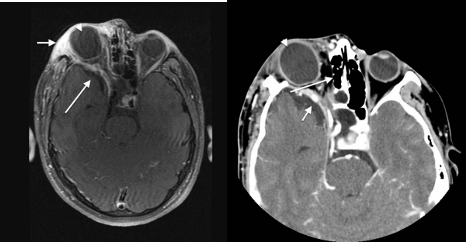

• 시각신경교종 (Optic glioma)

• 뇌 MRI: 시각로, 뇌간, GP, thalamus, IC, 소뇌 등에 T2WI 신호 증강 병변